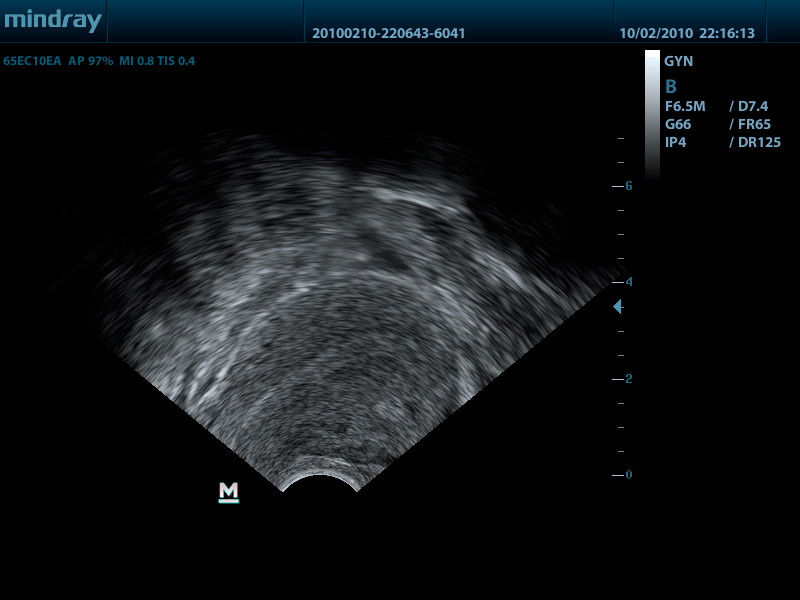

- Внутриполостной датчик 65EC10EA, 3.0 - 12.5 МГц, радиус кривизны 10 мм